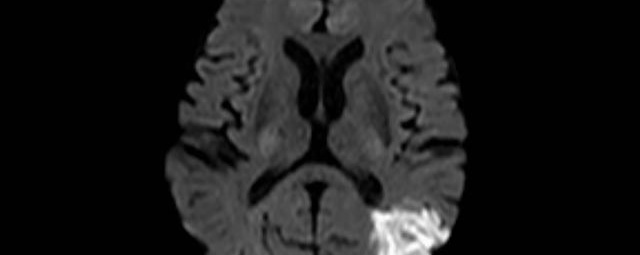

- Diffusionswichtung

- Perfusionswichtung

- Suszeptibilitätswichtung

- MR-Spektroskopie

Diese Verfahren werden bei verschiedenen Fragestellungen in verschiedenen Körperregionen in die Messprotokolle sinnvoll eingefügt. Teilweise können dadurch Differenzierungenverschiedener krankhafter Prozesse verbessert werden.